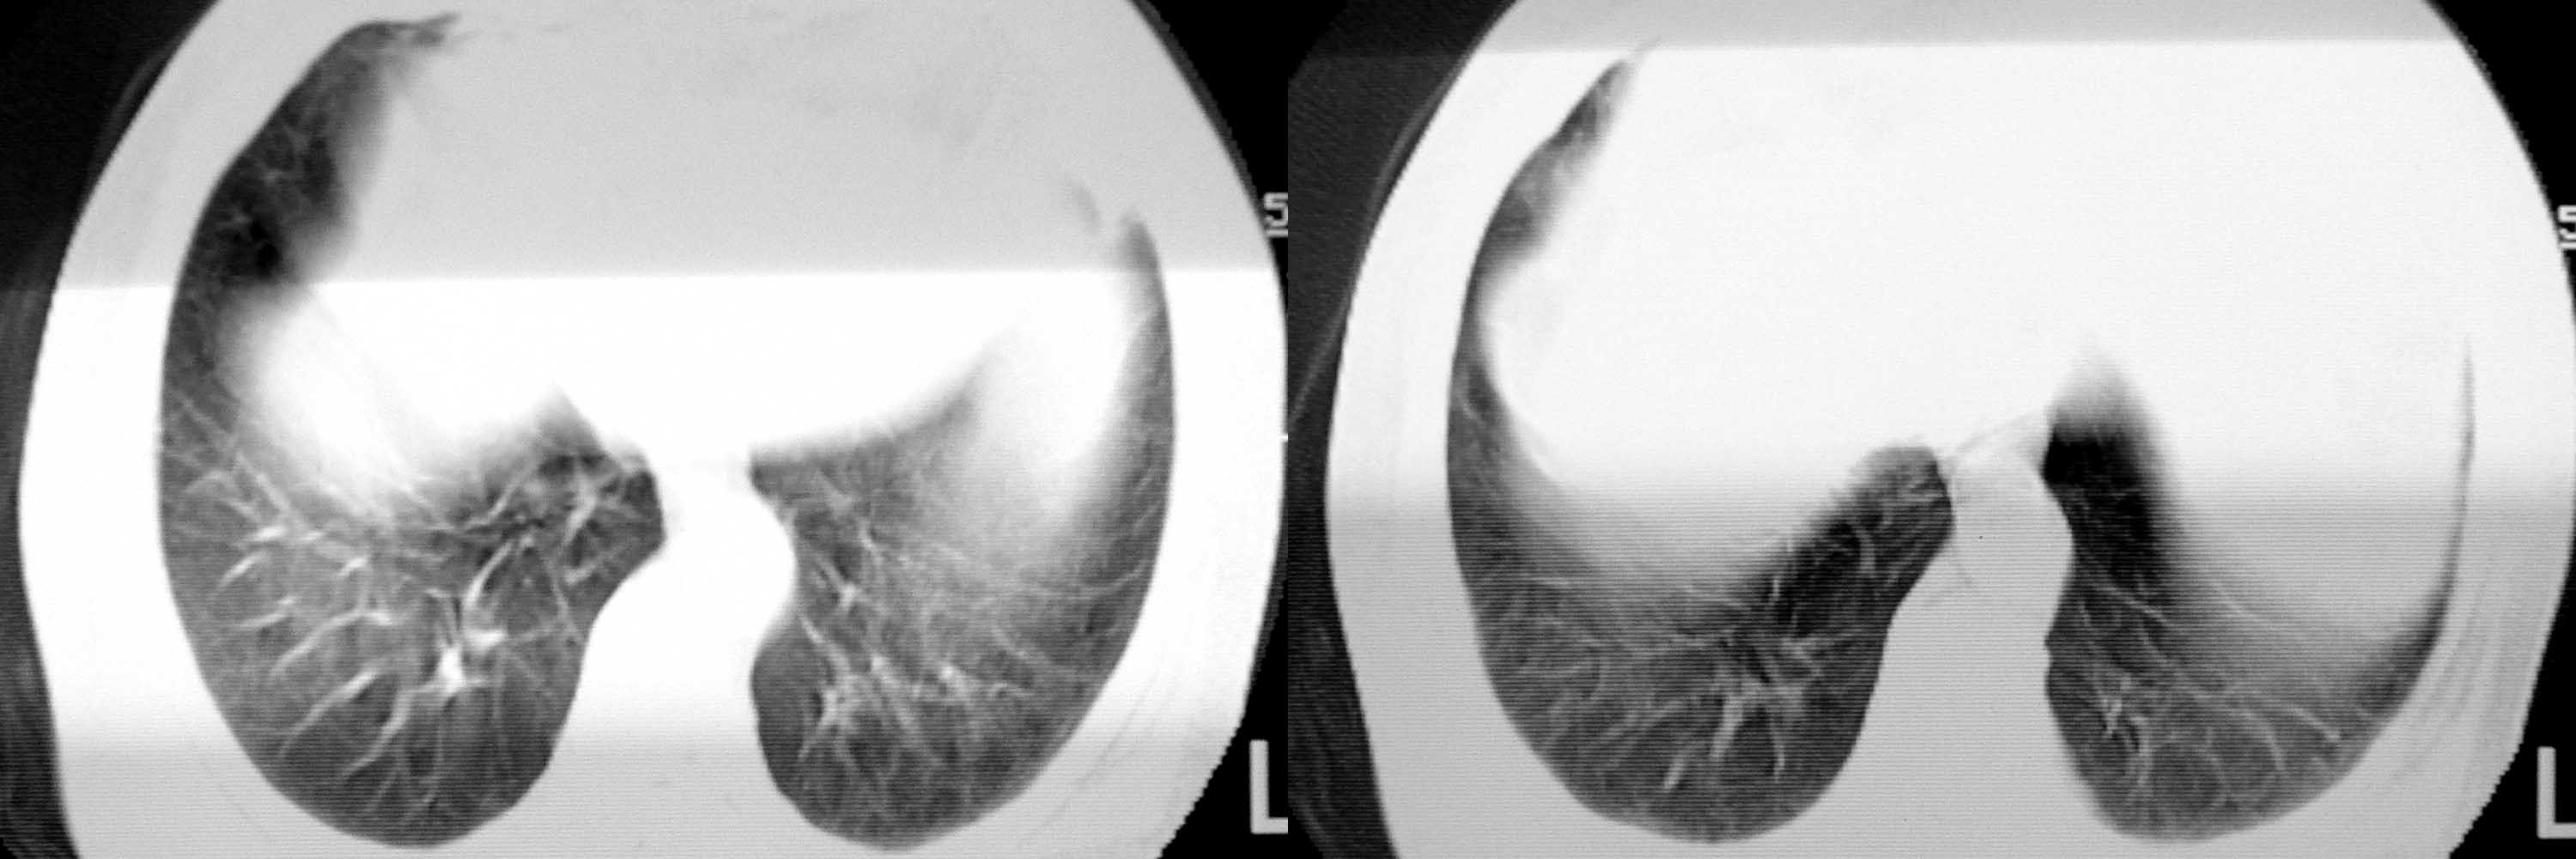

女78岁咳嗽咳痰无咳血平片报右上肺不张、慢支、肺气肿、请老师们帮忙看看,箭头所指是什么?是占位吗?有肺气肿吗?谢谢

箭头所指考虑血管影;纵隔内及双肺门区多发淋巴结钙化;不支持肺气肿。

箭头所指考虑血管影(头臂血管);纵隔内及双肺门区多发淋巴结钙化;不支持肺气肿。